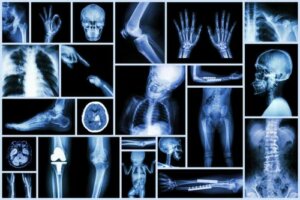

Come qualsiasi altro studio di imaging, i raggi X ci consentono di conoscere aspetti del corpo dei bambini che non possiamo vedere ad occhio nudo.

Al pronto soccorso, una radiografia ci aiuta a confermare la diagnosi di una frattura, la presenza di un corpo estraneo nelle vie aeree, o definire che il dolore addominale richiede un trattamento chirurgico.

In altre aree e discipline mediche, i raggi X hanno portato benefici infiniti e possiamo esserne certi. Inoltre, sono studi rapidi ed economici, disponibili nella stragrande maggioranza dei centri sanitari e che, in generale, non richiedono procedure di sedazione o anestesia.